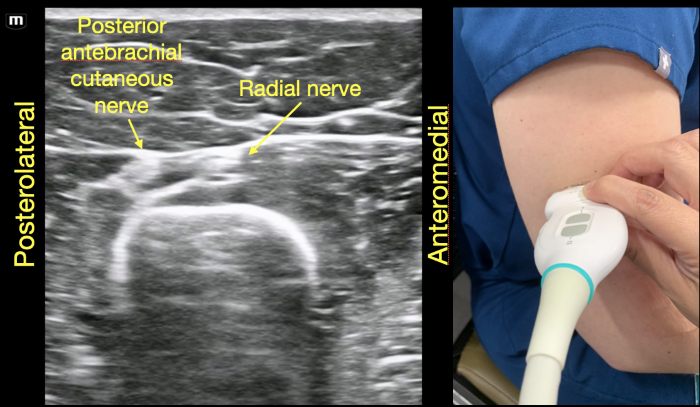

As the probe is moved distally along the spiral groove, the posterior cutaneous nerve of the forearm can be seen branching from the radial nerve just prior to the lateral intermuscular septum (Figure 7D). In Video Clip 1, the radial nerve passes from the triceps into the biceps through the linear echogenic lateral intermuscular septum, which is a hyperechoic connective tissue layer separating the dorsal and anterior compartment of the arm.13

RadialNerve-Image6 Aug2024.pngFigure 6. Radial nerve joins the posterior cutaneous branch of the forearm proximal to the lateral intermuscular septum in the dorsal compartment of the arm.